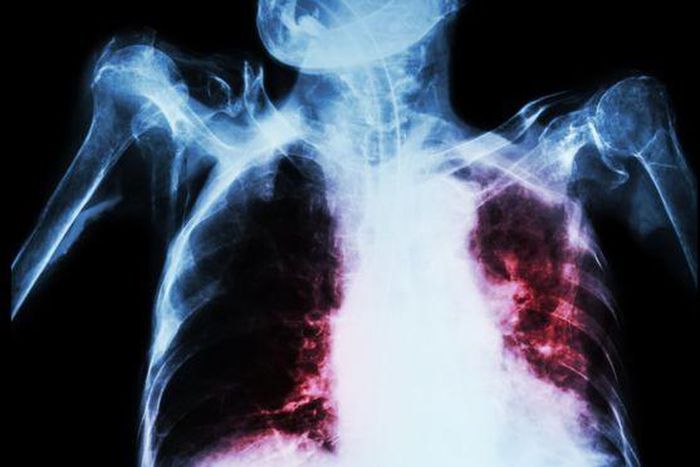

TB can affect the lungs